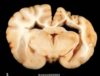

Name the pathologic process.

Hydrocephalus

Name the pathologic process.

Hydrocephalus

Name the pathologic process.

Hydrocephalus